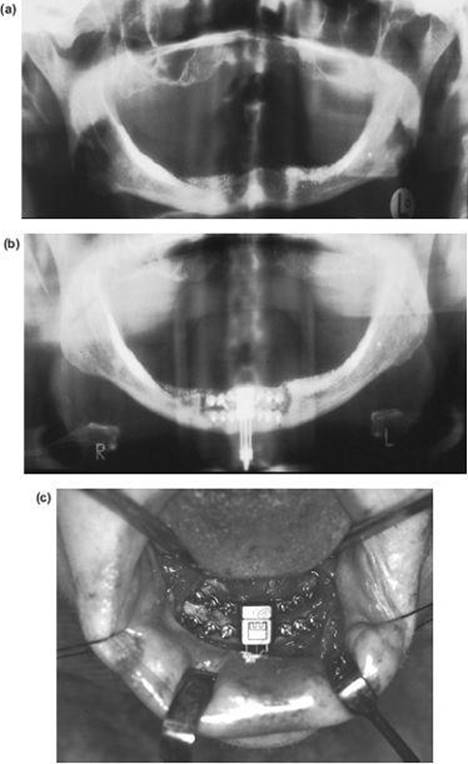

The Inverted L Osteotomy

Indications

This operation is valuable when there is a need to increase both the ramus height and body length at the same time, especially when the sagittal split osteotomy is not possible. Such cases are usually gross congenital mandibular hypoplasia or, occasionally, acquired hypoplasia following condylar fractures or when previous surgery has disturbed the bony anatomy. The operation differs in concept from the sagittal split procedure in that a bone graft is inserted to make up the deficiency.

Technique

1. The surgical approach is exactly the same as for the extraoral subsigmoid osteotomy (steps 1-6 and see Figure 9.4) except that the bone cut is made from the anterior border of the ascending ramus, passing distally, to behind the estimated position of the lingula then downwards to the lower border anterior to the angle, i.e. to the antegonial notch (Figure 9.7a).

2. With bilateral deformities the approach is repeated on the opposite side.

3. The mandible is then temporarily fixed into occlusion. Where the maxilla is normal this presents no problems. However, if there is a deformity of the maxilla this must be corrected before the inverted L and fixed with bone plates.

Mobilising the small mandible into the desired anterior position can be difficult and is facilitated by drilling a hole bilaterally in the lower border of the mandible just anterior to the osteotomy cut and passing a 0.5 mm traction wire to be attached to heavy forceps. When anterior traction is applied, explore the deep tissues medial to the mandible with a finger to find any restraining bands of periosteum, muscle or ligament. These must be vigorously divided with the finger to ensure stability.

4. With the proximal condylar fragment confirmed to be in the fossa, the gap created can be measured, and a template formed with sterile paper or card.

Figure 9.7 (a), (b)

5. An interpositional graft is now obtained. The ideal source is cortico-cancellous bone from the iliac crest. A solid cancellous graft can be used but the incorporation of one cortex provides reassuring stability. Some surgeons use split rib for the gap. Two miniature bone plates provide excellent rigidity and form (Figure 9.7b).

6. A vacuum drain is inserted and the wound is closed in layers.

7. The intermaxillary fixation is released and the pack removed.

Note: Any mandible which requires lengthening with an inverted L osteotomy also requires an augmentation genioplasty.